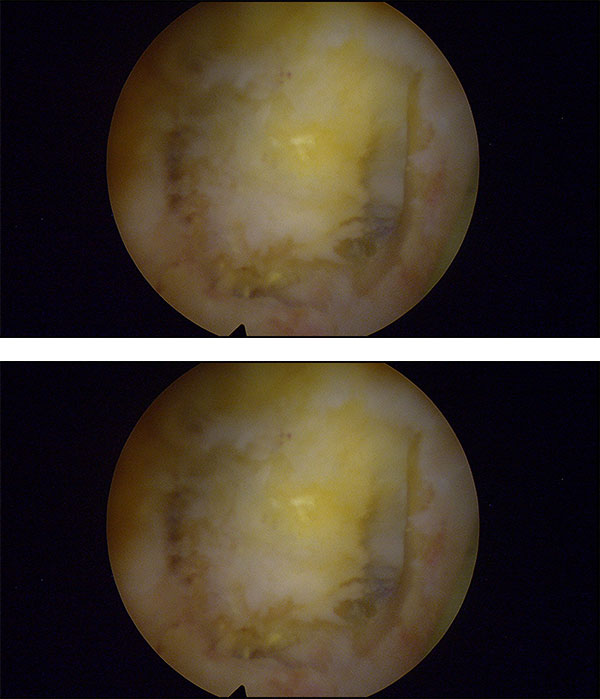

Con esta operación lo que pretendíamos conseguir era abordar el canal, retirarle en el quiste entre la quinta raíz y la S1 el quiste sinovial y en la cuarta raíz quitarle la hernia y liberarle las raíces.

Esta operación lo que nos permitió fue revisarle todos los nervios a la paciente, comprobar todo lo que sería el saco y ver que no había ningún tipo de compresiones. Durante la operación quitamos las hernias y vimos en qué condiciones estaba el resto del canal.